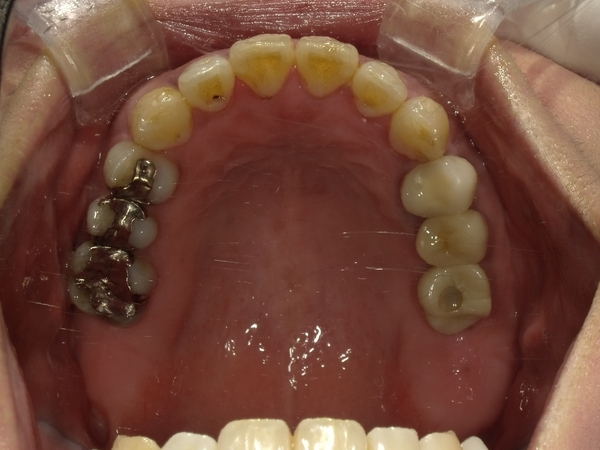

〇ご相談内容:上の前歯が内側に入っている、下の歯のがたつきが気になる〇矯正の種類:マウスピース型矯正「インビザライン」〇治療期間:14週間(約3ヵ月)〇治療費用:44万円(税込)